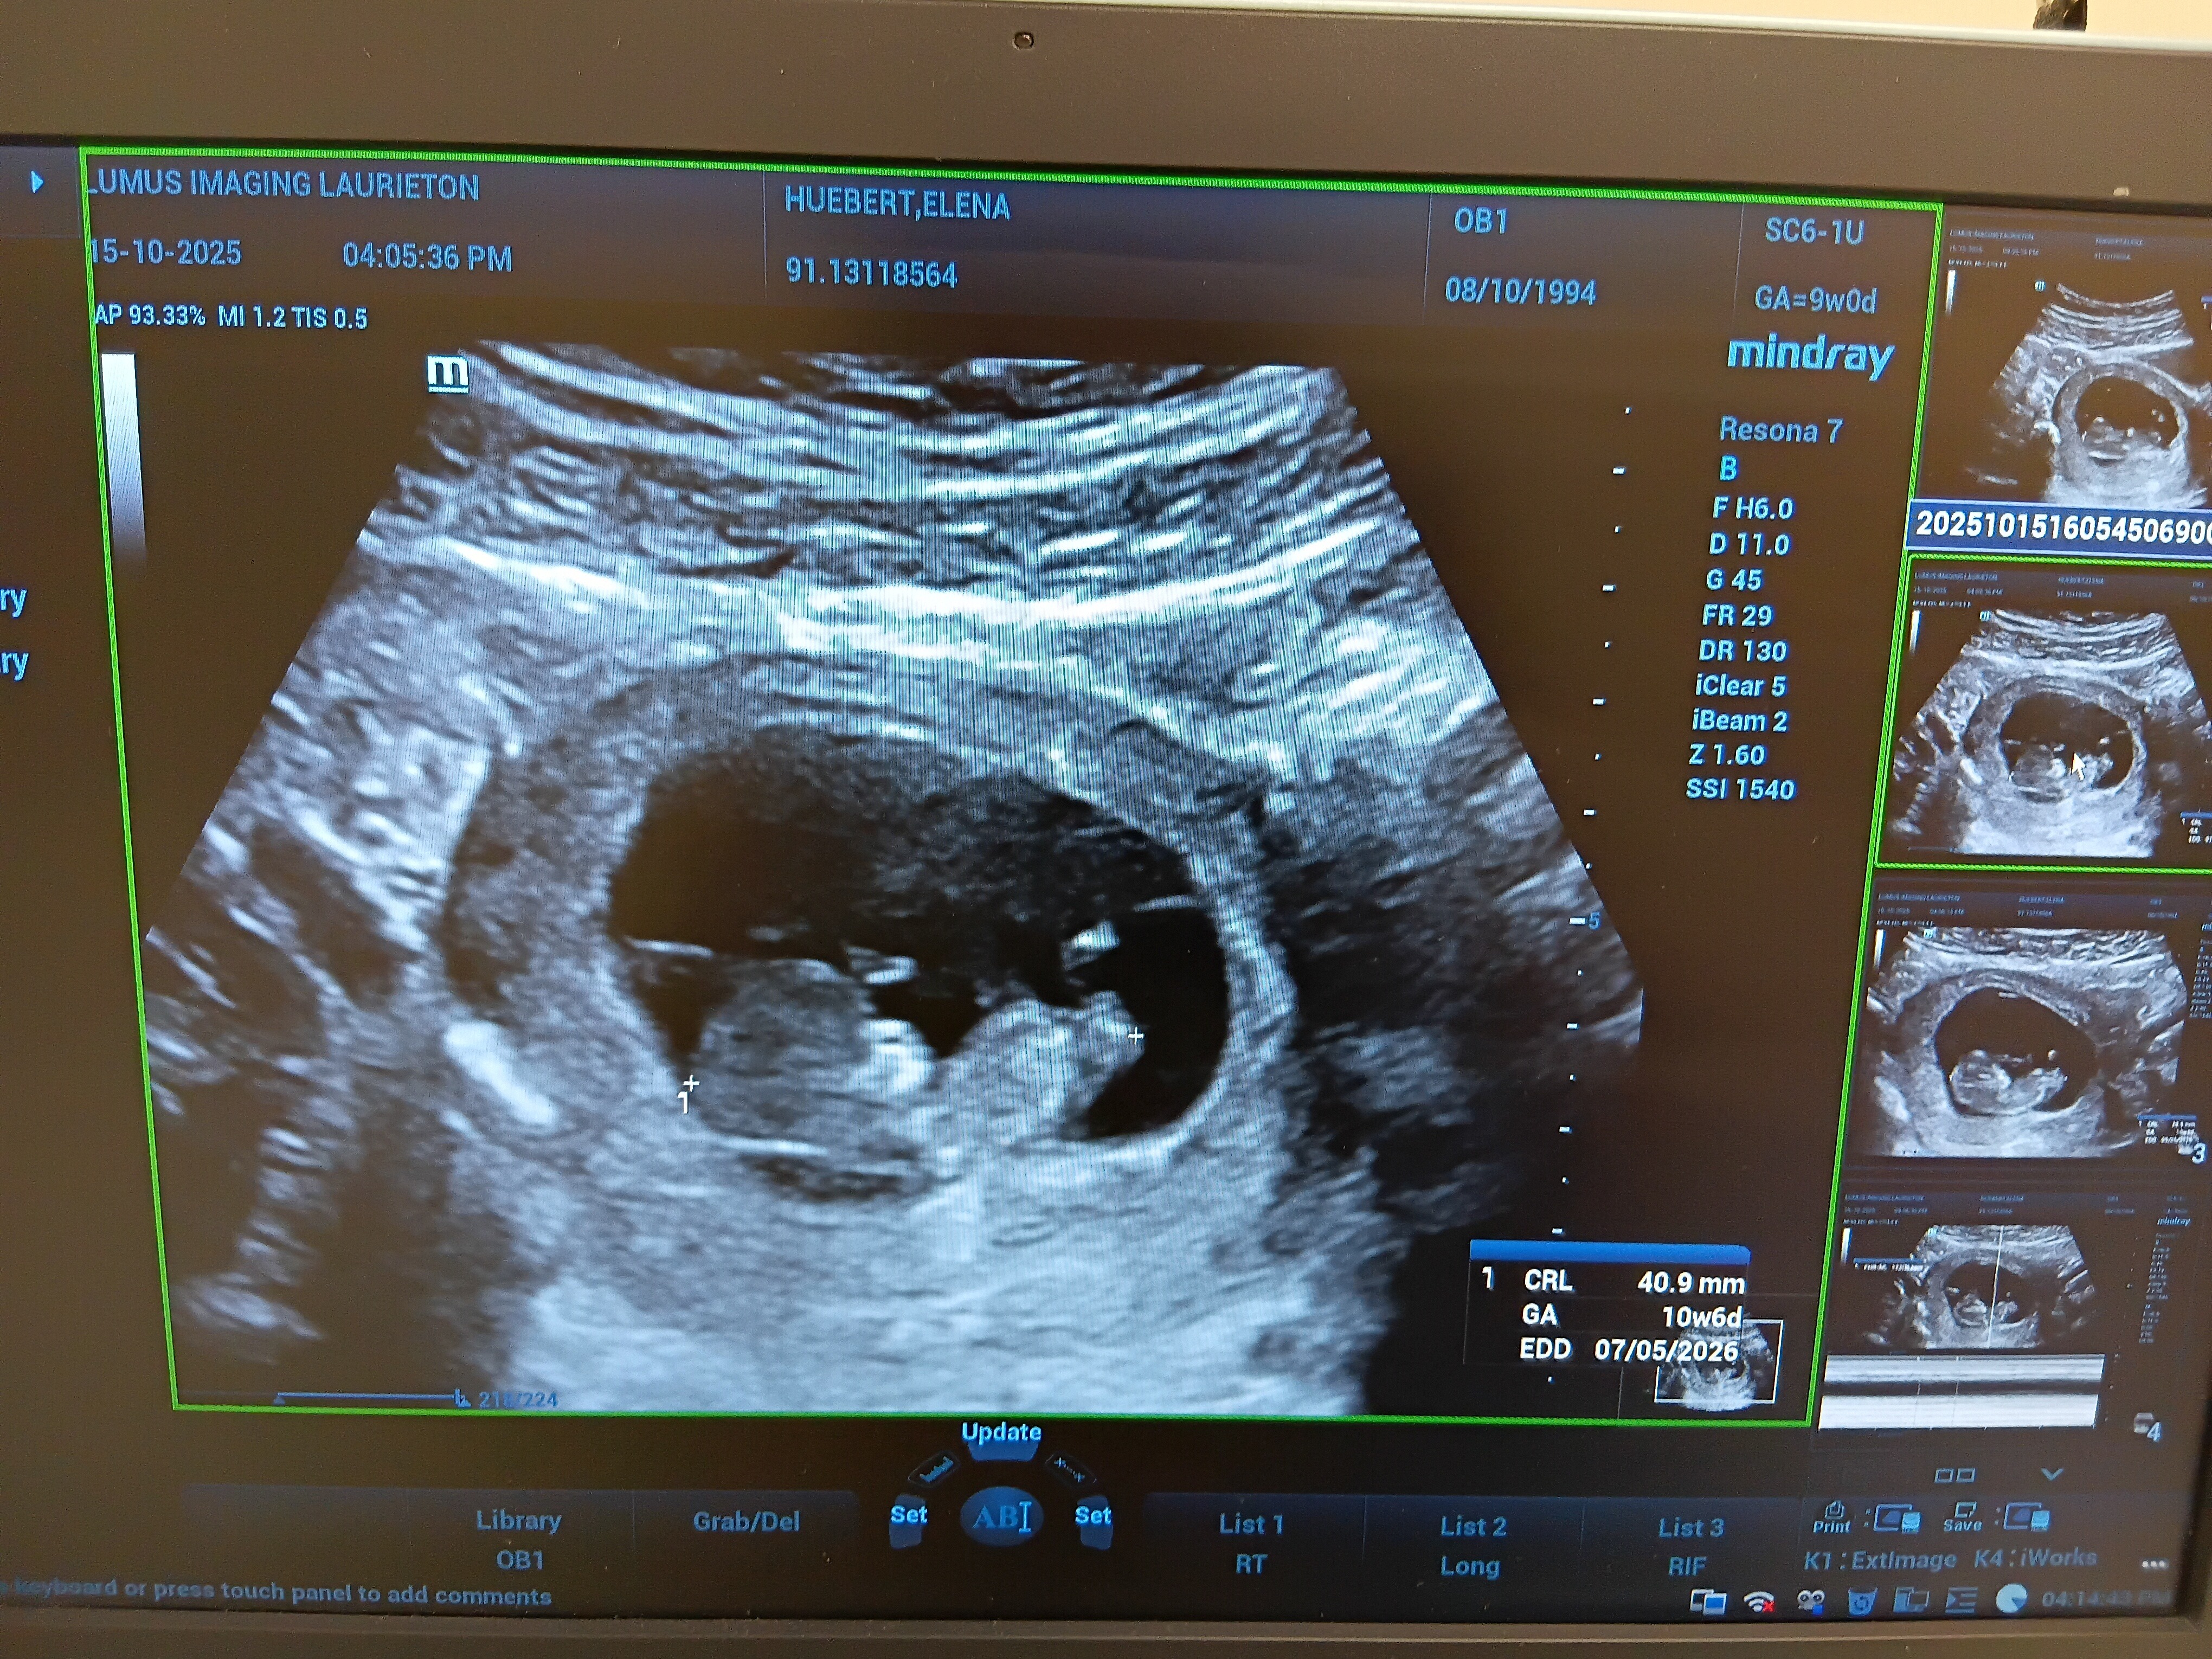

Hey pals! Some of you may know that we have been going down the consciousness conception journey for a while now and have shared in the joy and grief that is all a part of trying to bring life into the world. Well after exactly 1 year our miracle baby is finally nestled in and will be making an appearance in May 2026!